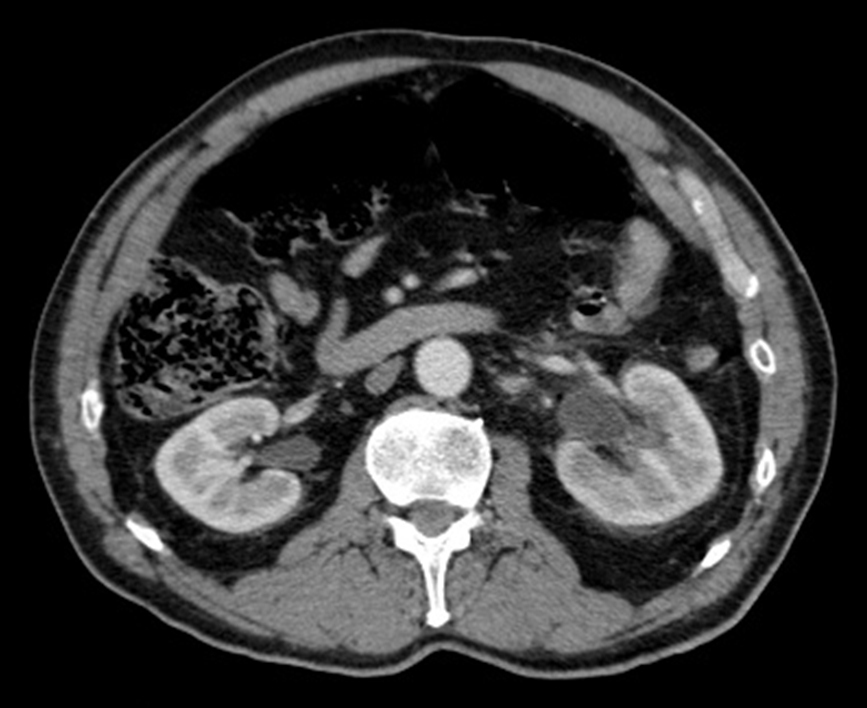

À l’arrivée au SAU : pression artérielle = 114/72 mmHg ; fréquence cardiaque = 75 bpm ; température = 36,5 °C.